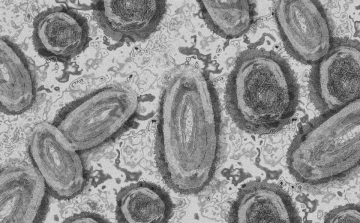

Tovább nőtt a majomhimlő-fertőzöttek száma Magyarországon

Újabb két embernél igazolt majomhimlő-fertőzést a Nemzeti Népegészségügyi Központ (NNK) a 33. héten - augusztus 15-től 21-ig -, ezzel 64-re nőtt a magyarországi esetek száma.

Meghaladta a 13 ezret a majomhimlő-fertőzöttek száma az Egyesült Államokban

Meghaladta a 13 ezret a majomhimlő-fertőzöttek száma az Egyesült Államokban, a legtöbb esetet Kaliforniában és New York államban regisztrálták.

Megfertőződött a majomhimlővel egy gyerek Németországban

Megfertőződött majomhimlővel egy négyéves kislány Németországban - jelentették kedden német hírportálok az országos közegészségügyi intézet (RKI) adatai alapján.

Tovább nőtt a majomhimlő-fertőzöttek száma Magyarországon

Újabb kilenc, 23-50 éves férfinél igazolták a majomhimlő-fertőzést Magyarországon, ezzel 42-re nőtt a fertőzöttek száma - közölte a Nemzeti Népegészségügyi Központ (NNK) csütörtökön az MTI-vel.

Tovább nőtt a majomhimlő magyar fertőzöttjeinek száma

Újabb hat embernél diagnosztizálták a majomhimlő vírusát, így harmincra emelkedett az igazolt fertőzöttek száma Magyarországon - közölte a Nemzeti Népegészségügyi Központ (NNK) pénteken az MTI-vel.